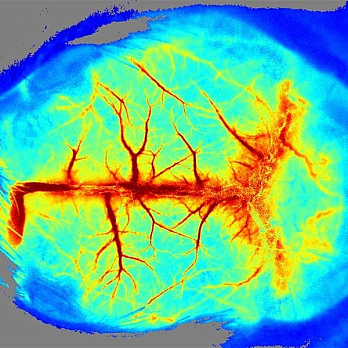

Системы MOIS предназначены для захвата и анализа изображений биолюминисцентных и флуоресцентных сигналов образцов тканей и живых организмов, полученных в формате in vivo и in vitro. Благодаря использованию высокочувствительной макрокамеры и высококачественных фильтров MOIS можно получать отличные изображения в режиме реального времени. Система имеет высокую производительность, а четыре канала (синий, зеленый, красный и ближнекрасный) позволяют получить визуализацию широкого спектра флуоресцентных белков и красителей, включая GFP и ICG. Анализ люминисцентных сигналов осуществляется при помощи соответствующего ПО, входящего в комплект поставки прибора. Простая конструкция системы MOIS отличается удобством в работе, быстротой и надежностью.

- Мониторинг хода заболевания в живом организме, изучение с помощью изображений распространение и роста опухолевых клекток;

- определение эффективности и биологического распределения лекарственных препаратов, частиц наноформата и других молекул;

MOIS HT визуализирует флуоресценцию в видимом (VIS) и инфракрасном (NIR) спектре, биолюминисценцию in vivo и in vitro